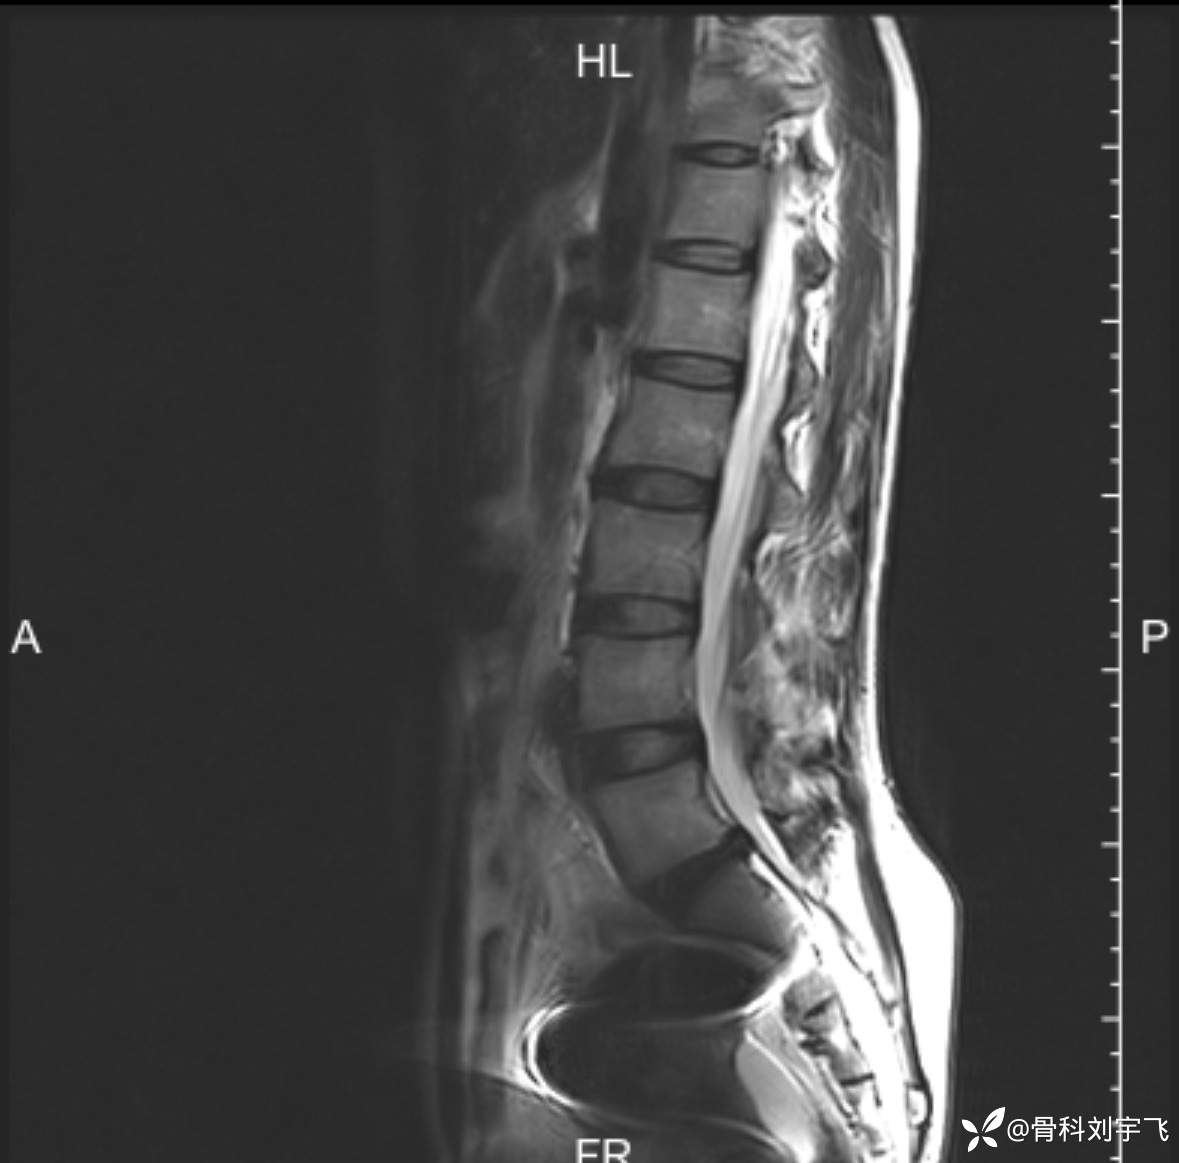

辅助检查:腰椎核磁 膝关节核磁

临床诊断:腰5骶1中央型突出